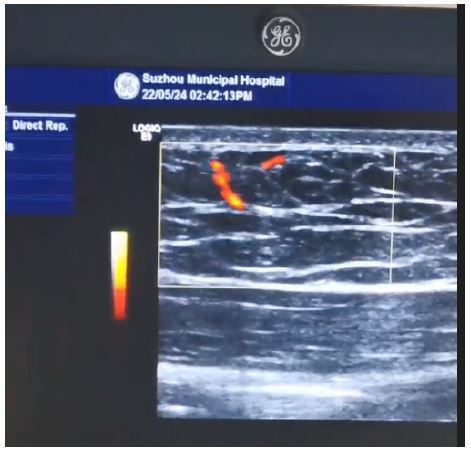

Instruments: A GE Logiq9 ultrasound diagnostic instrument was used. Vascular examination conditions included a linear array probe with a frequency of 8–12 MHz. The parameters were adjusted to the most sensitive settings without generating noise and then fixed (Figure 1).

Figure 1: Measurement of perforating branches of abdominal wall by color ultrasound.

Patients were placed in a supine position with one side of the abdominal wall selected. The examination area was defined with the upper boundary 2 cm above the umbilicus, the lower boundary 6 cm below the umbilicus, the medial boundary along the midline of the abdomen, and the lateral boundary along the anterior axillary line. With coupling gel applied, the probe was used to gently press the skin to locate the inferior epigastric artery (with its internal diameter measured 6 cm below the umbilicus) and then trace the course of the vessel upward to find perforators. According to the commonly used oblique outward and upward design direction for paraumbilical flaps, the larger perforators in the outward or outward-upward direction were selected, and their diameter and Peak Systolic Velocity (PSV) were measured. The course of the perforating vessels was observed. When the perforator penetrated from the deep fascia, it was marked perpendicularly on the skin as point a, and when the perforator approached the entry point into the skin, it was marked as point b. The length of the line segment ab was the projection length of the perforator on the body surface (measurements are shown in Figure 2 and Figure 3). All these procedures were performed by the same ultrasound physician to ensure consistency in measurements and quality control. According to the measurement values, the dominant perforator with a larger internal diameter, higher flow velocity, and greater length was selected as the pedicle vessel for designing the interregional flap. In this group, a total of 15 cases were measured, and the results are recorded in Table 2.

The design axis of the paraumbilical perforator flap often extends from the paraumbilical perforator point to the ipsilateral inferior angle of the scapula [12]. In this context, we selected perforators oriented laterally or in the superolateral direction as the primary focus for measurement. According to the concepts of angiosomes and perforasomes proposed by Taylor and Crystal, an angiosome resembles a tree-like structure in three-dimensional form. However, the spatial structure of blood vessels after they perforate the deep fascia is represented by perforasomes. Between two adjacent perforasomes, the vessels theoretically have smaller diameters and lower density, which can be referred to as the choke zone of the angiosome [13,14]. This corresponds to the anatomical supply area. In ultrasound imaging, this can be approximated as the region where the perforator, while supplying blood to the skin, becomes gradually undetectable in the subcutaneous or near-dermal layer. This concept serves as the primary basis for measuring the length of abdominal wall perforators. The average perforator length measured was 5.56 cm, with a 95% confidence interval of 4.6 to 6.5 cm. The estimated anatomical supply area of the DIEAP flap extends approximately 5.5 cm or slightly further laterally from the perforator point (as indicated by the red line in Figure 2).